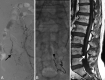

Background and purpose: Spinal arteriovenous shunts below the conus constitute 3 types of lesions, which have previously been mainly described in case reports, given their rarity, and are sometimes misdiagnosed. The purpose of this study was to describe the features of each type and compare these types as to epidemiologic features, clinical and radiologic presentations, treatment, and outcomes in a consecutive series of 48 cases.

Materials and methods: The prospectively collected data bases of 2 referral centers for spinal vascular lesions were retrospectively reviewed. Spinal arteriovenous shunts below the conus were defined as all dural and intradural shunts below the conus medullaris. Clinical features, radiologic findings, treatment results, and clinical outcomes were assessed.

Results: There were filum terminale arteriovenous fistulas in 11 patients (22.9%), radicular arteriovenous shunts in 7 patients (14.6%), and spinal dural arteriovenous fistulas in 30 patients (62.5%). Radicular arteriovenous shunts presented at a younger age (P = .017) and with a higher incidence of back pain symptoms (P = .037). A tethered spinal cord was found in 54.5% of patients with filum terminale arteriovenous fistulas and 23.3% of patients with spinal dural arteriovenous fistulas. After treatment, the angiographic complete obliteration rate was 89.4% and spinal function was improved significantly (P < .001).

Conclusions: Three groups of spinal arteriovenous shunts below the conus can be differentiated according to clinical and radiologic features. Filum terminale arteriovenous fistulas are frequently associated with dysraphic malformations, which may suggest a particular embryologic origin.